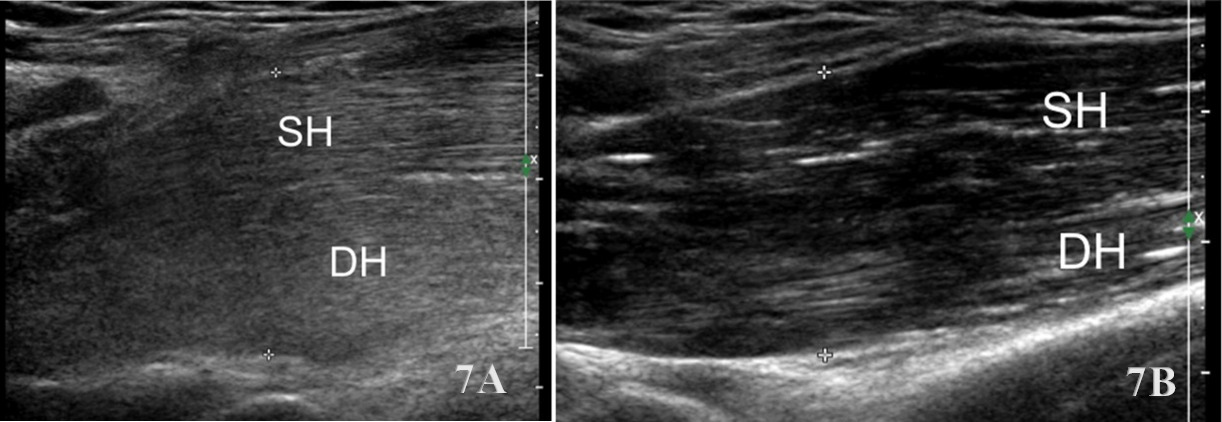

Examination Protocol

The brachialis is assessed using a linear high-frequency transducer (10–15 MHz), placed transversely over the distal anterior upper arm to identify the brachialis deep to the biceps brachii. In the short-axis (SAX) view, begin at the distal third of the humerus, visualizing the biceps superficially and the brachialis as a deeper, more hypoechoic structure adjacent to the humerus. Rotate the transducer 90° for a long-axis (LAX) view, tracing the muscle proximally toward the mid-humerus and distally to its insertion on the ulnar tuberosity.

Normal Sonographic Appearance

Normally the brachialis tendon is viewed in both LAX and SAX views. The brachialis tendon can be seen distally at the ulnar attachment. The hyperechoic outline of the ulna will be seen below the brachialis. The brachialis tendon will be more hyperechoic in appearance, while proximally from the ulna the brachialis muscle will be hypoechoic tissue. In the LAX view the muscle should be fibrillar. The soundhead may need to be toggled at the distal tendons insertion to avoid anisotropy. Dynamic visualization can be performed with resisted elbow flexion and forearm pronation and supination.20,21